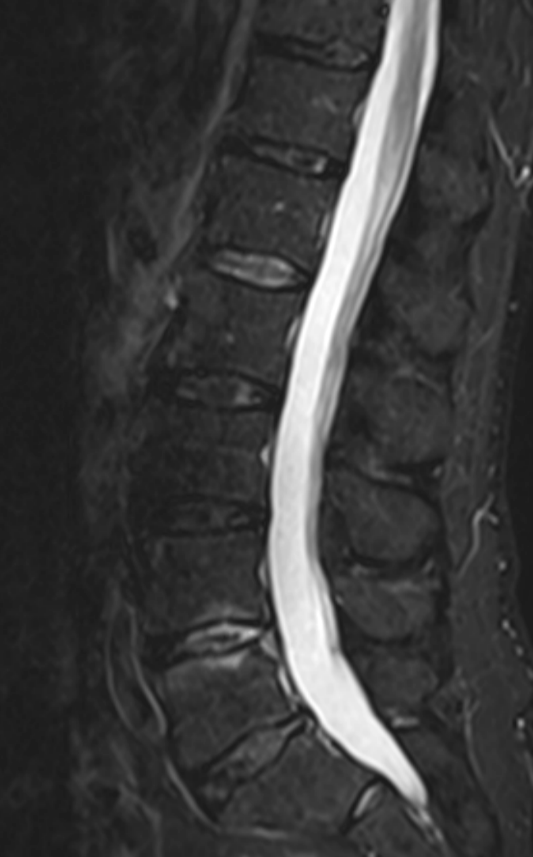

3. Discitis